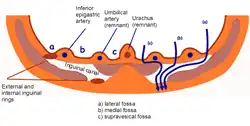

The umbilical artery regresses after birth. A portion obliterates to become the medial umbilical ligament (not to be confused with the median umbilical ligament, a different structure that represents the remnant of the embryonic urachus). A portion remains open as a branch of the anterior division of the internal iliac artery. The umbilical artery is found in the pelvis, and gives rise to the superior vesical arteries. In males, it may also give rise to the artery to the ductus deferens which can be supplied by the inferior vesical artery in some individuals.

Tail end of human embryo, twenty-five to twenty-nine days old. Inguinal fossae